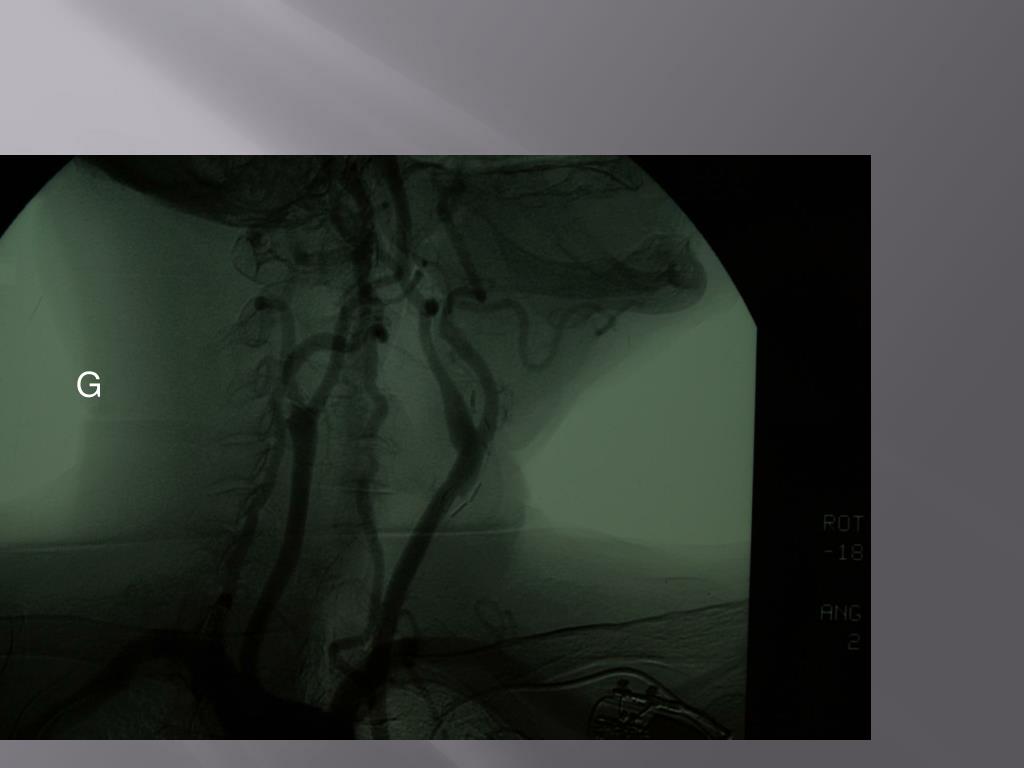

21. With the use of statins in ACTS-1 • The evidence of stroke fell strongly in the medical arm • But it fall strongly as well is the CEA arm. • So the difference is still highly significant

27. EVERSION Cochrane 2003

28. TECHNICEversion Notre opinion Pour LESS RESTENOSIS NO CLINICAL BENEFIT SURGEON CHOICE

36. CONTROLE PER-OPERATOIREAngiographie per-op